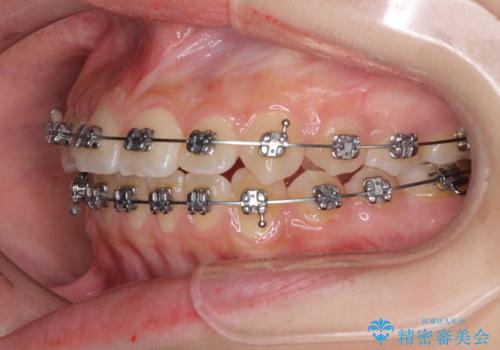

前歯のクロスバイト メタル装置での矯正治療

- メタルブラケット

- 前歯のクロスバイトを気にして来院された患者様です。

前歯の叢生を解消するスペースを獲得するために上顎左右の親知らずを抜歯し、メタルブラケットにて矯正治療を行うこととしました。

当初は1年半程度の治療期間を想定していましたが、上下の正中を合わせていく過程で奥歯の咬みにくさが続いてしまい、2年以上の治療期間を要することとなりました。